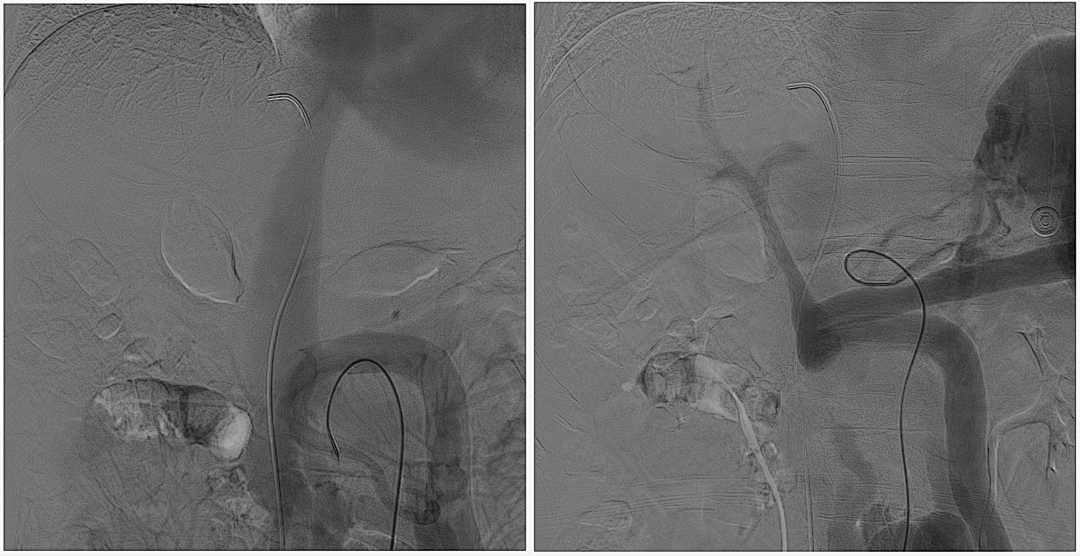

至腸系膜上動脈行間接門靜脈造影,未見門靜脈顯影,可見巨大異常分流道,遂至脾動脈行間接門脈造影可見門靜脈異常纖細,腸系膜下靜脈見異常分流道形成

以微導管行肝動脈標記輔助穿刺,門靜脈造影顯示血流呈離肝狀態(tài)

超選至腸系膜下靜脈異常分流道,予以栓塞18mm的Amplatzer vascular plug及適量25%生物膠,造影示異常分流道消失